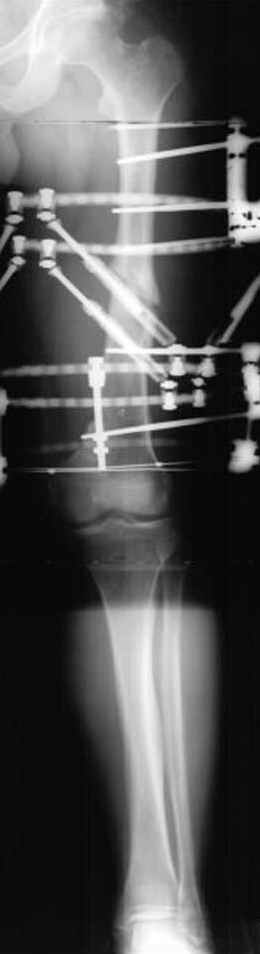

пластическая модель; и коррекция бедра аппаратом Илизарова.